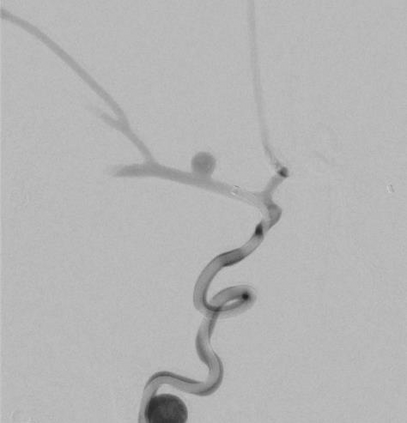

Objective: The objective of this work is to introduce and demonstrate the effectiveness of a novel sensing modality for contact detection between an off-the-shelf aspiration catheter and a thrombus. Methods: A custom robotic actuator with a pressure sensor was used to generate an oscillatory vacuum excitation and sense the pressure inside the extracorporeal portion of the catheter. Vacuum pressure profiles and robotic motion data were used to train a support vector machine (SVM) classification model to detect contact between the aspiration catheter tip and a mock thrombus. Validation consisted of benchtop accuracy verification, as well as user study comparison to the current standard of angiographic presentation. Results: Benchtop accuracy of the sensing modality was shown to be 99.67%. The user study demonstrated statistically significant improvement in identifying catheter-thrombus contact compared to the current standard. The odds ratio of successful detection of clot contact was 2.86 (p=0.03) when using the proposed sensory method compared to without it. Conclusion: The results of this work indicate that the proposed sensing modality can offer intraoperative feedback to interventionalists that can improve their ability to detect contact between the distal tip of a catheter and a thrombus. Significance: By offering a relatively low-cost technology that affords off-the-shelf aspiration catheters as clot-detecting sensors, interventionalists can improve the first-pass effect of the mechanical thrombectomy procedure while reducing procedural times and mental burden.